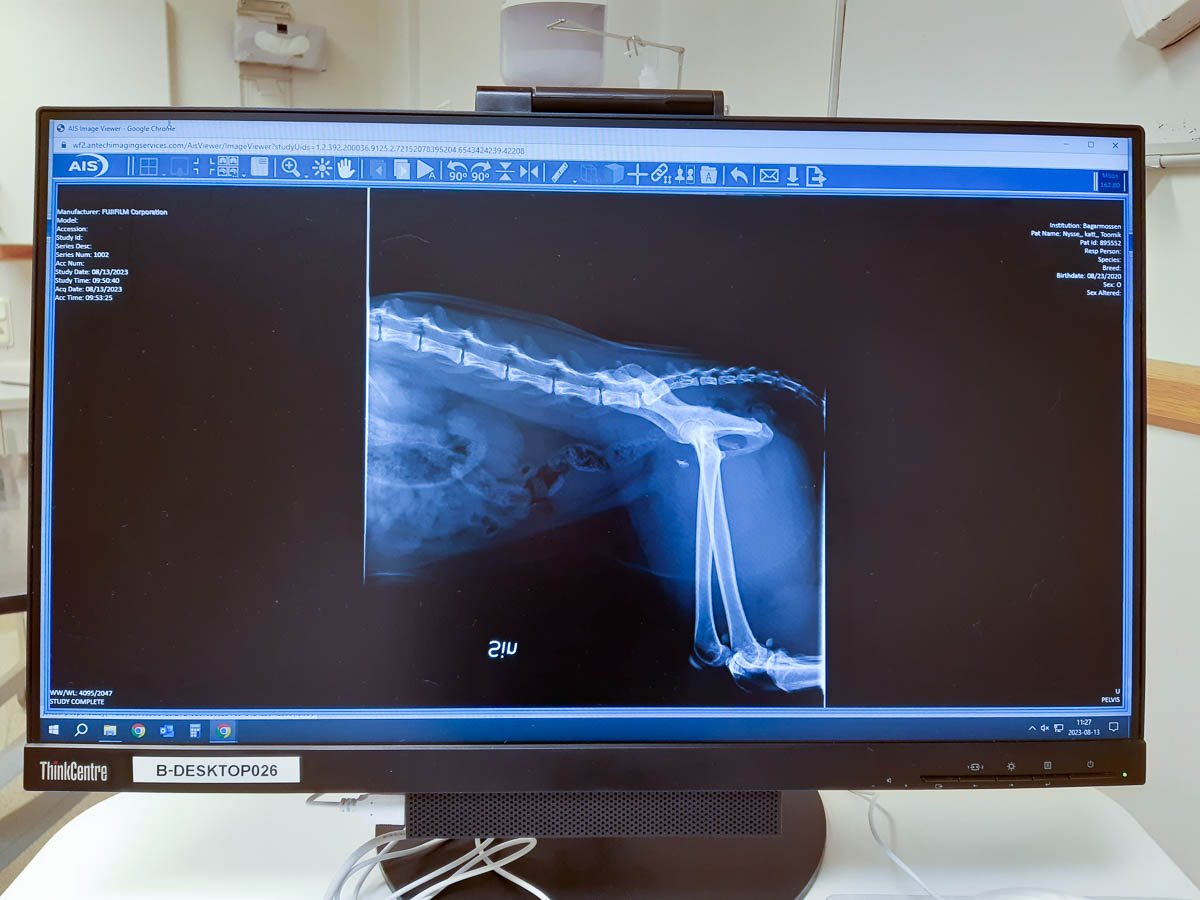

Hours later, he’d gotten heavy-duty painkillers, and been examined and x-rayed. The poor kitty has a fractured pelvis. With the painkillers he finally got some proper rest, and we left him at the hospital for surgery tomorrow morning. We should get to bring him home tomorrow evening or the morning after that. And then he has four to six weeks of cage rest ahead of him, for recovery.